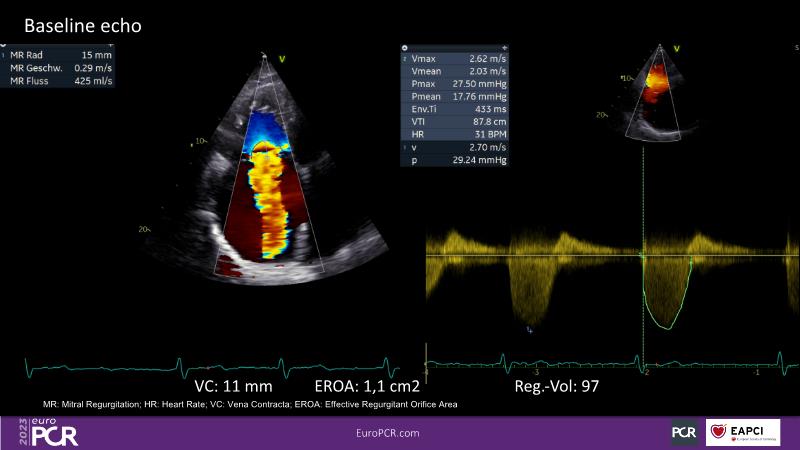

Tailoring tricuspid regurgitation patient treatment with the PASCAL Precision system

- To discuss the different tricuspid regurgitation phenotypes that can be treated with the PASCAL Precision repair system

- To participate in a case-based discussion using the PASCAL Precision repair system for the treatment of tricuspid regurgitation